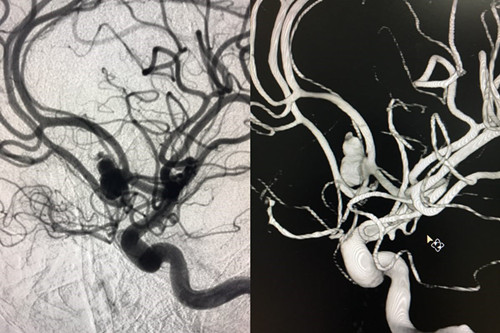

术前造影

患者赵某,8月28日因“蛛网膜下腔出血”入住我院神经外科。入院时意识呈浅昏迷,且意识障碍进行性加重伴随右侧瞳孔散大,曲友直教授团队根据颅脑CT判定患者为动脉瘤引起的蛛网膜下腔出血。由于动脉瘤在人体内像个定时炸弹,随时会再次破裂,危险性非常大。能否及时为患者实施动脉瘤手术,避免动脉瘤继续破裂,从源头遏制患者病情继续恶化的可能性,直接关系到患者的预后。曲教授团队制定了详细的诊疗计划,在最短时间内为患者行侧脑室外引流术,并及时为患者实施了全脑血管造影,结果证实了术前判断,是大脑前交通动脉瘤,分上下两叶、宽颈。考虑到患者脑肿胀明显,基础状态差,急诊行开颅夹闭手术风险极高,曲友直教授团队反复评估、综合考虑后为患者实施了双导管技术宽颈动脉栓塞术。实施双导管技术避免支架辅助对前交通宽颈动脉瘤进行栓塞,术后患者无须长期口服抗血小板及抗凝药物、为患者术后赢得了进一步康复的机会、减少了长期服药的经济负担。手术过程十分顺利,术后患者病情稳定,正在进一步恢复治疗中。